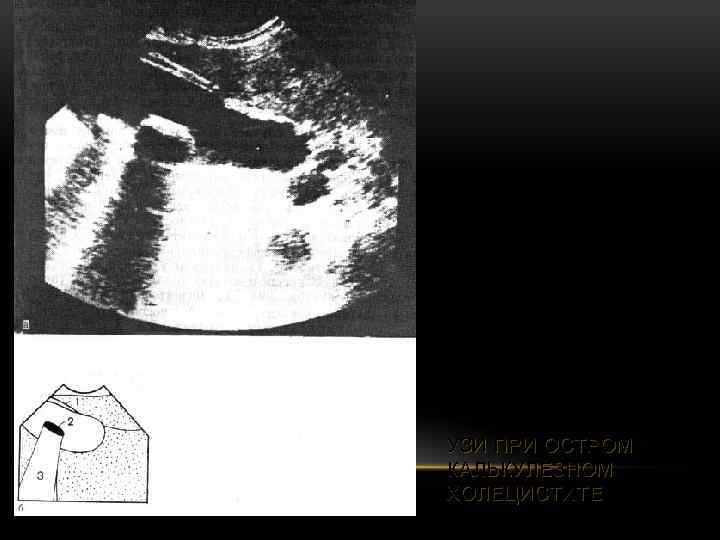

УЗИ ПРИ ОСТРОМ КАЛЬКУЛЕЗНОМ ХОЛЕЦИСТИТЕ

УЗИ ПРИ ОСТРОМ КАЛЬКУЛЕЗНОМ ХОЛЕЦИСТИТЕ